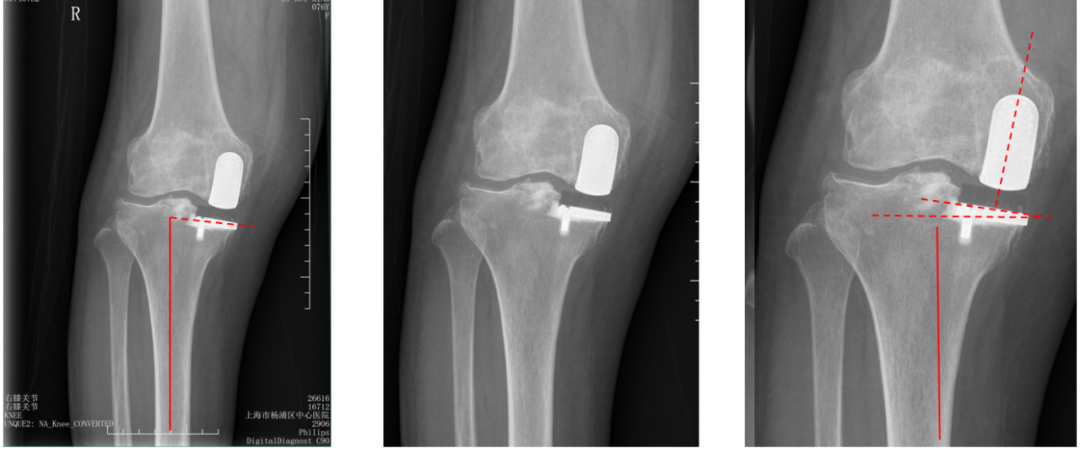

股骨假体偏内放置

AP位胫骨与股骨假体位置:股骨假体无内外内翻,中轴线与胫骨假体中线不一致,偏内侧。

侧位片股骨假体后倾不足

侧位片假体位置:胫骨假体后倾3°,完全覆盖胫骨平台前后缘,股骨假体后倾30°,股骨后髁覆盖不足。

胫骨假体偏厚

胫骨垫片厚度合适:术前外翻畸形矫正至轻度内翻。